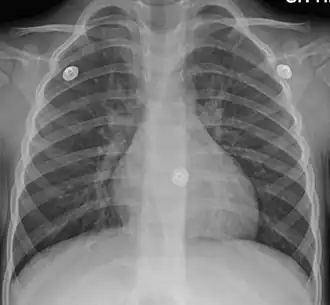

In more than 90% of cases, the cause is a viral infection.[1] These viruses may be spread through the air when people cough or by direct contact.[2] Risk factors include exposure to tobacco smoke, dust, and other air pollution.[2] A small number of cases are due to high levels of air pollution or bacteria such as Mycoplasma pneumoniae or Bordetella pertussis.[1][9] Diagnosis is typically based on a person's signs and symptom.[4] The color of the sputum does not indicate if the infection is viral or bacterial.[1] Determining the underlying organism is typically not needed.[1] Other causes of similar symptoms include asthma, pneumonia, bronchiolitis, bronchiectasis, and COPD.[1][7] A chest X-ray may be useful to detect pneumonia.[1]

Mild peribronchial cuffing as seen in viral bronchitis